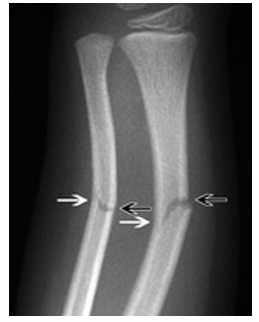

Radial and Ulna shaft ORIF Indications and Post-op

Indications: Displaced closed #’s

Post Operation:

Cast 6 weeks, commence AROM and strengthening post cast removal